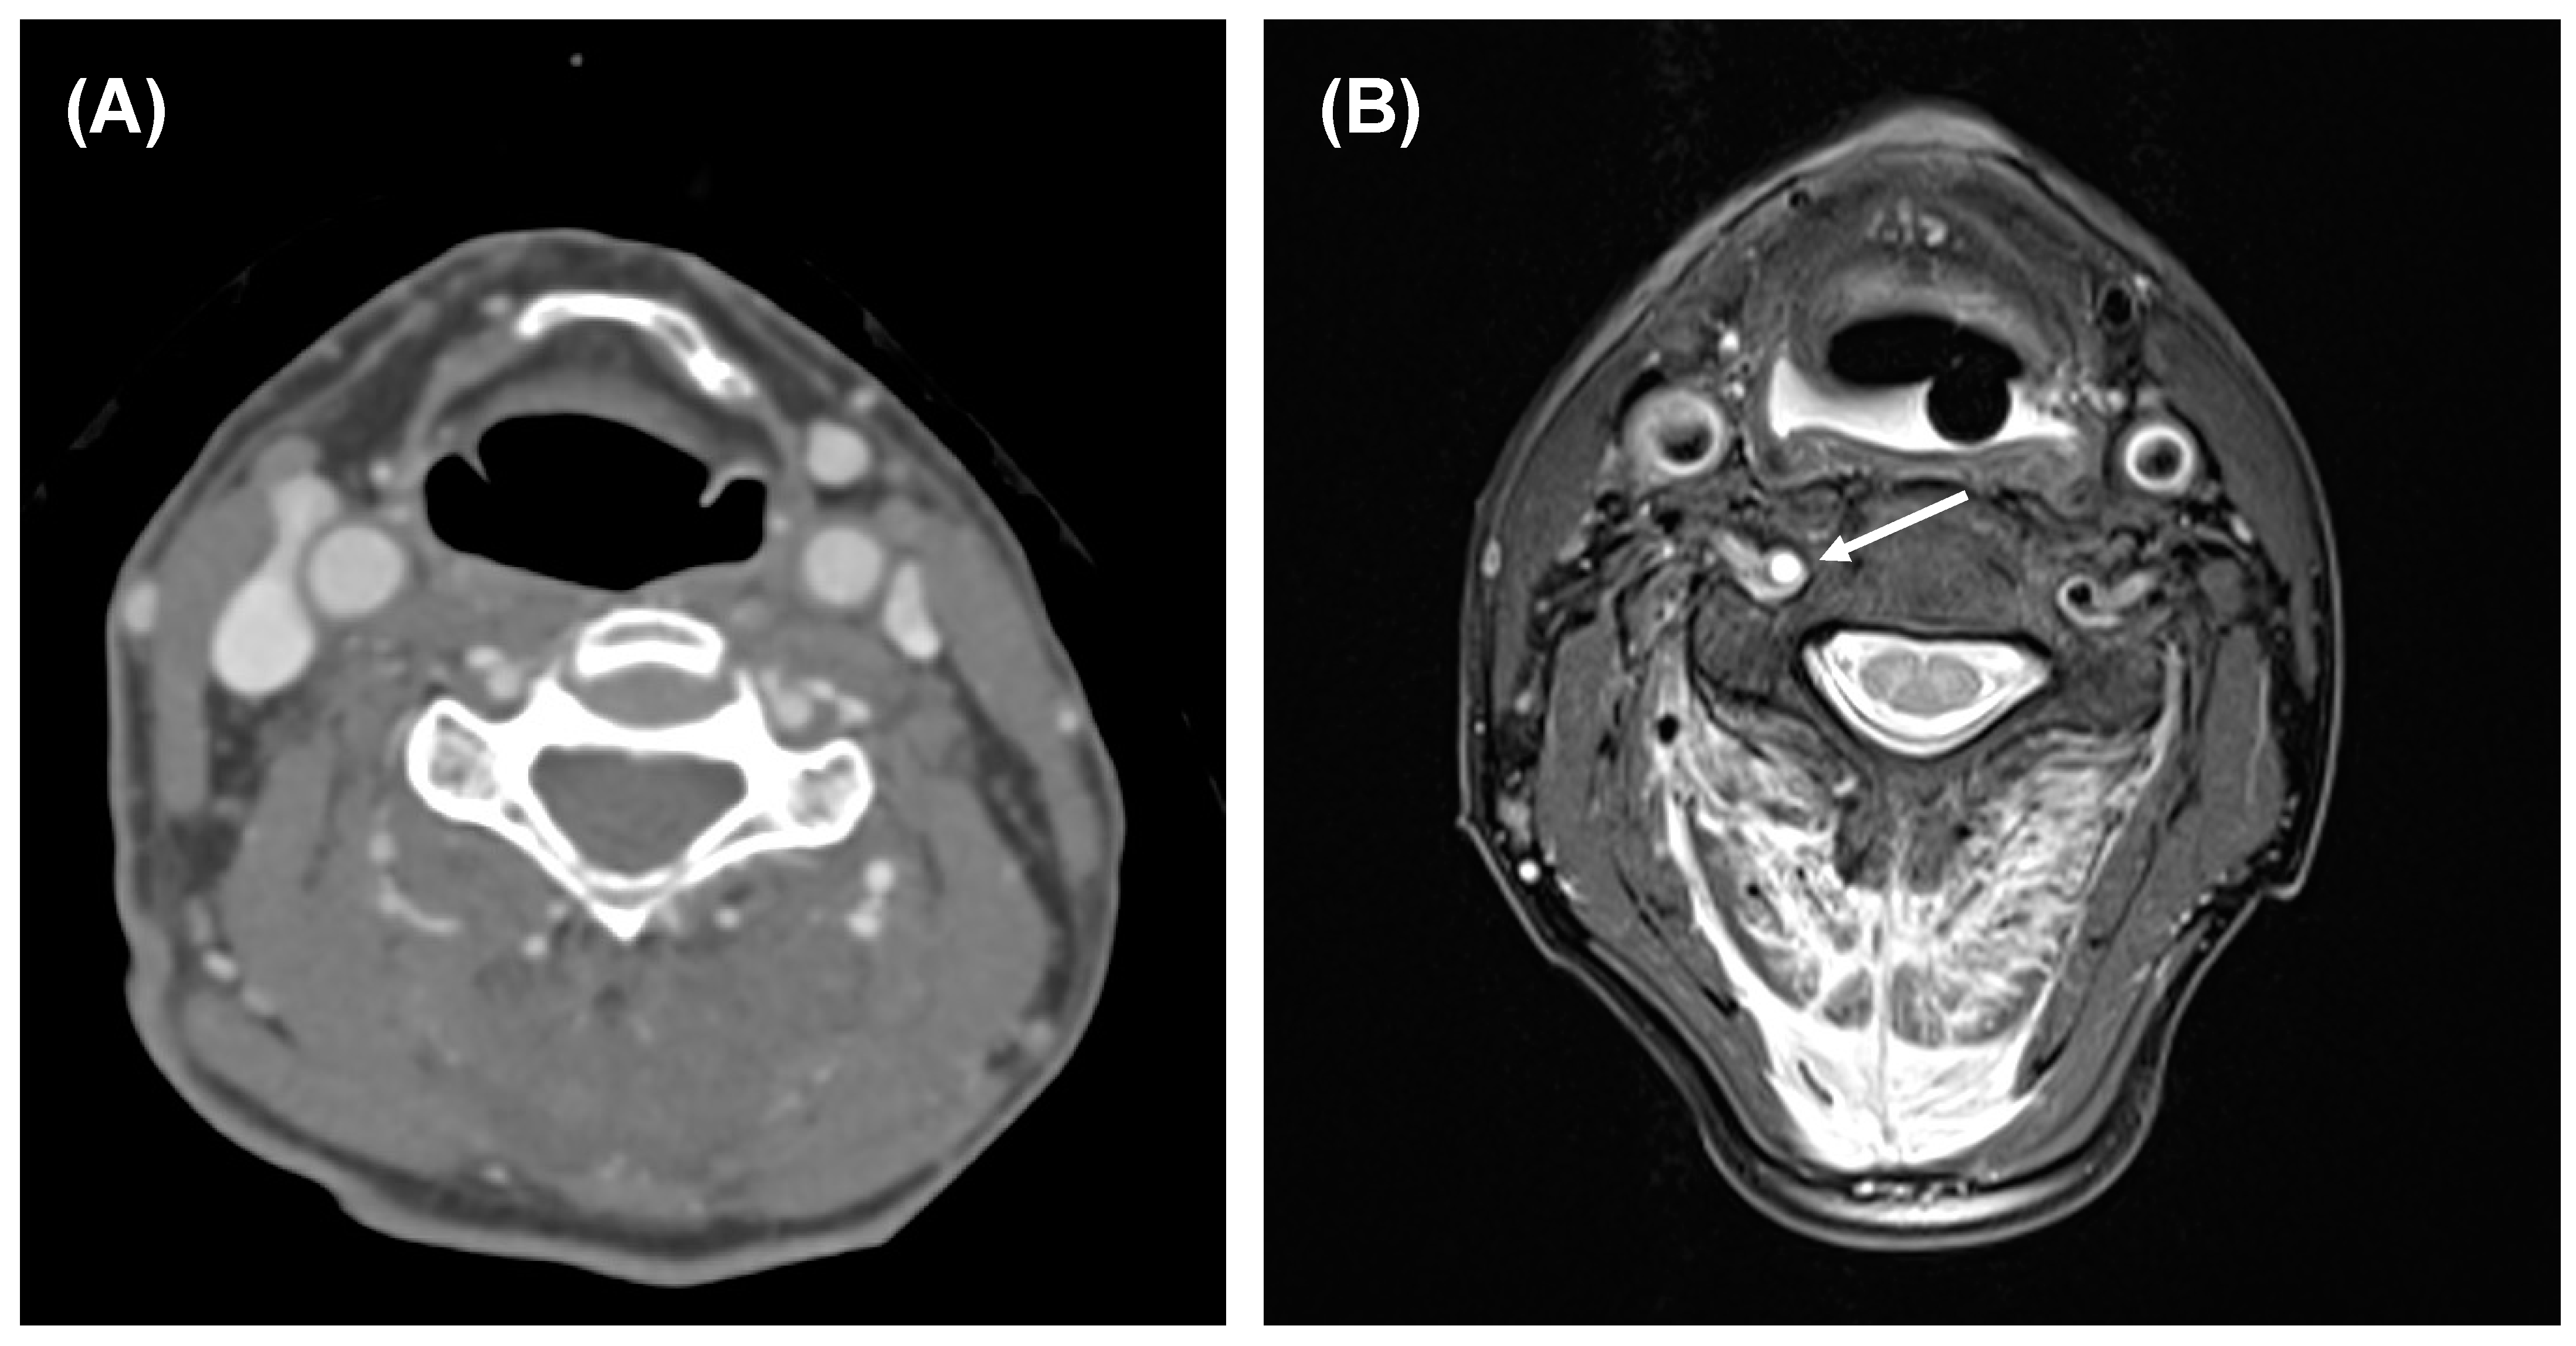

- Popp, D.; Thiedemann, C.; Baumler, W.; Ernstberger, A.; Alt, V.; Schicho, A. Modified split-scan computed tomography (CT) diagnostics of severely injured patients: First results from a level I trauma center using a dedicated head-and-neck CT-angiogram for the detection of cervical artery dissections. J. Clin. Med. 2020, 9, 2568. [Google Scholar] [CrossRef] [PubMed]